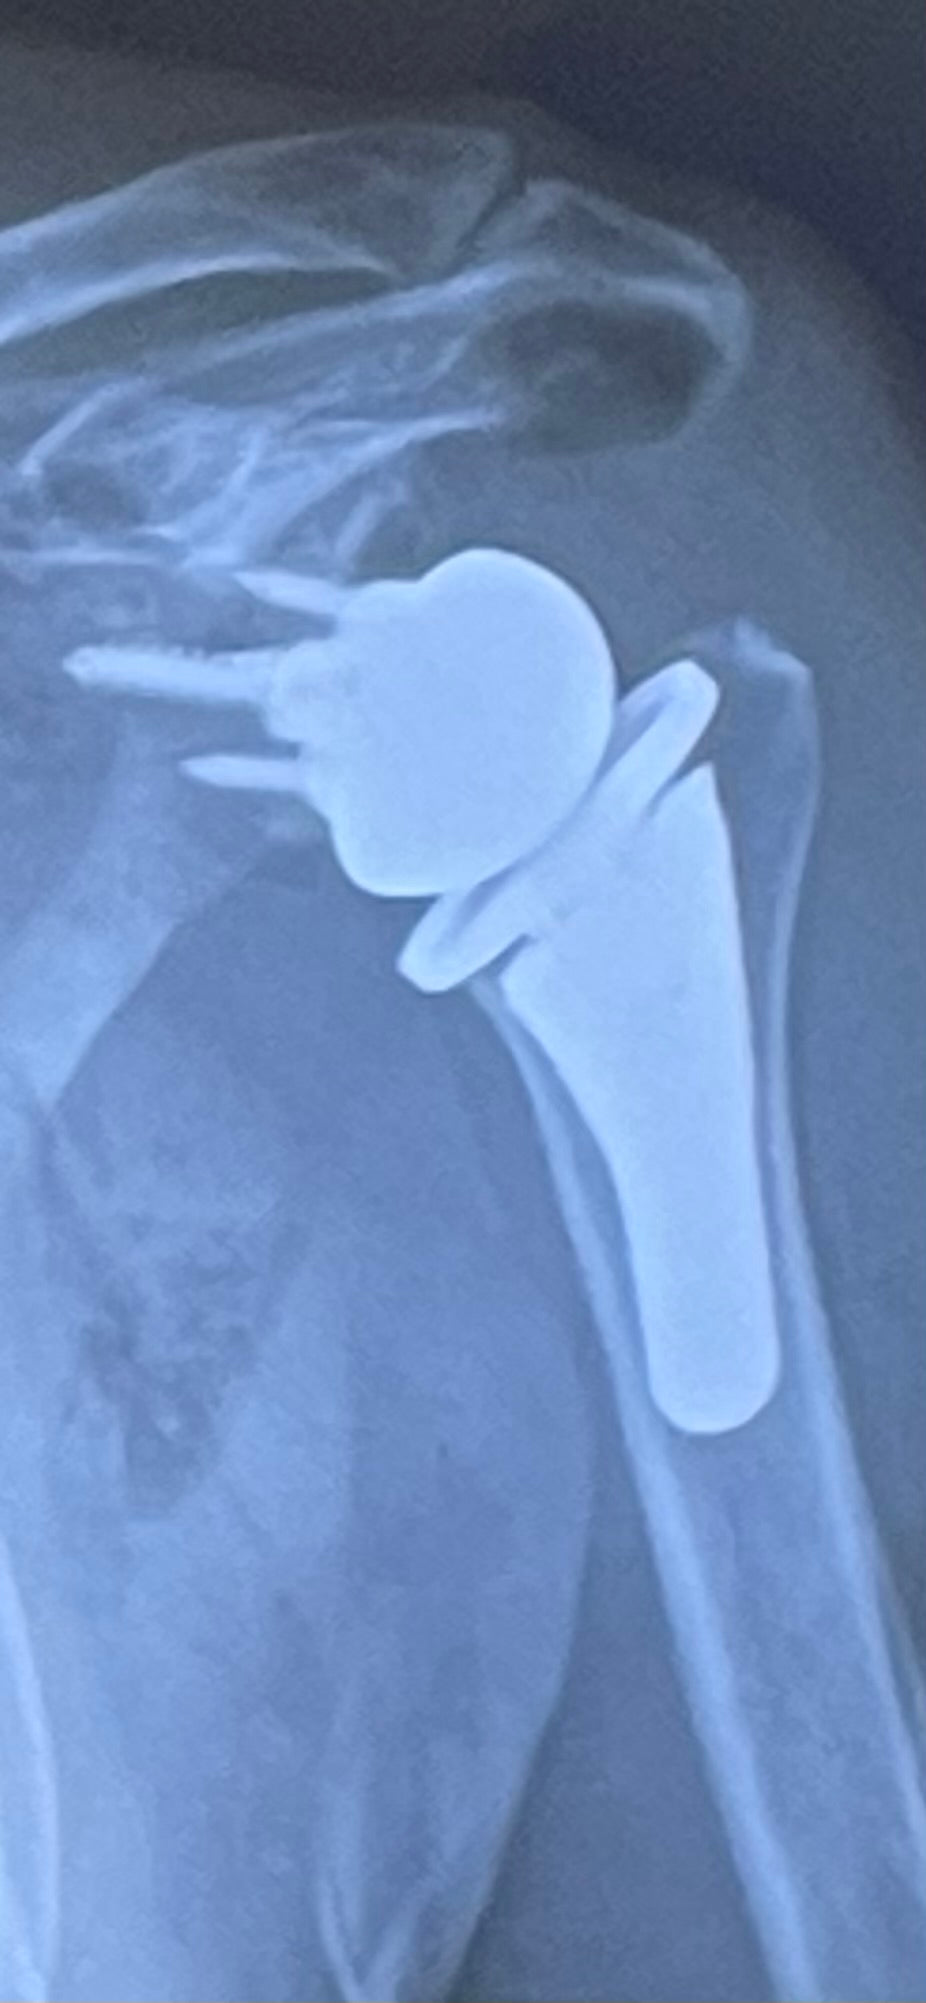

After being diagnosed with advanced degenerative joint disease in his left shoulder more than 4 years ago, Kevin began a learning experience surrounding the various treatments offered to correct this debilitating and painful condition. This workshop will give an overview of the various procedures and options offered to correct and improve shoulder functions, paying special attention to surgical options. Kevin will share his personal experience about having a Reverse Total Replacement – its pros, cons and outcomes.